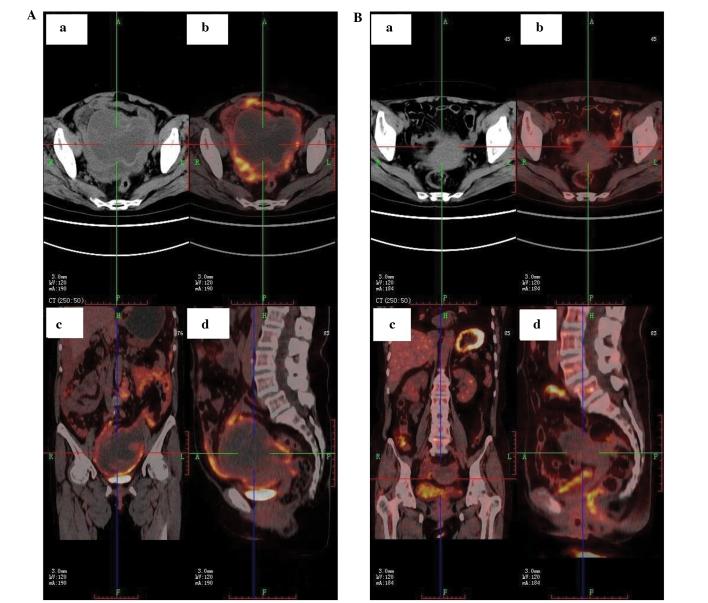

The current study presents the case of a 68-year-old female patient who received biological intensity-modulated radiotherapy (BIMRT) and neoadjuvant chemotherapy for multiple peritoneal metastases of ovarian cancer. The International Federation of Gynecology and Obstetrics disease stage was IIIc. In addition, the patient presented with urination and defecation difficulties. The result of tumor marker detection showed a carcinoembryonic antigen level of 348.2ng/ml, a cancer antigen 125 level of 2,091 U/ml and a cancer antigen 19-9 level of 113 U/ml. Computed tomography (CT) indicated and ovarian cystic or solid package, enlargement of multiple abdominal and retroperitoneal lymph nodes and abdominal cavity effusion. Positron emission tomography/CT indicated multiple internal organ metastases. The center of the ovarian cystic or solid package was considered to be a malignant tumor. A large amount of ascites were detected, as well as abdominal and retroperitoneal lymph node metastasis. The patient was treated with BIMRT at a total dose of 48 Gy, administered as a single 4.0-Gy dose 12 times. In addition, 100 mg cisplatin was administered as a peritoneal perfusion, followed by two cycles of 180 mg Taxol and 100 mg cisplatin. Furthermore, the enlargement of the lymph nodes was reduced and the tumor in the region of the ovary had decreased in size by 90%. The ascites had disappeared and the abdominal pain was greatly improved. At the time of writing this manuscript, the patient was well and without relapse. Therefore, modern radiotherapy techniques, such as BIMRT, may be considered as a beneficial treatment option for ovarian cancer patients with multiple peritoneal metastases in whom surgery is not suitable.

本研究报告了一例68岁女性患者,该患者因卵巢癌多发腹膜转移接受了生物调强放疗(BIMRT)和新辅助化疗。国际妇产科联盟疾病分期为IIIc期。此外,患者还出现了排尿和排便困难。肿瘤标志物检测结果显示,癌胚抗原水平为348.2ng/ml,癌抗原125水平为2091U/ml,癌抗原19-9水平为113U/ml。计算机断层扫描(CT)显示卵巢有囊实性包块,多个腹部和腹膜后淋巴结肿大以及腹腔积液。正电子发射断层扫描/CT显示多处内脏转移。卵巢囊实性包块的中心被认为是恶性肿瘤。检测到大量腹水以及腹部和腹膜后淋巴结转移。患者接受了总剂量为48Gy的BIMRT治疗,每次剂量为4.0Gy,共12次。此外,给予100mg顺铂进行腹腔灌注,随后进行两个周期的180mg紫杉醇和顺铂100mg治疗。此外,淋巴结肿大有所减轻,卵巢区域的肿瘤大小缩小了90%。腹水消失,腹痛明显改善。在撰写本手稿时,患者情况良好,无复发。因此,对于不适合手术的卵巢癌多发腹膜转移患者,现代放疗技术如BIMRT可被视为一种有益的治疗选择。